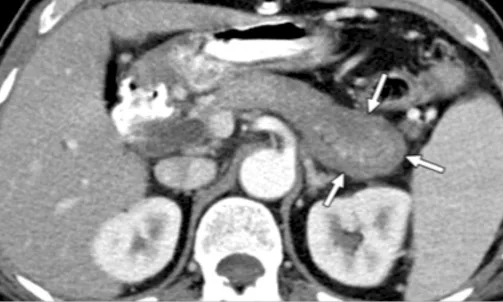

Les signes parenchymateux

1) Typiques : c’est le gros pancréas « saucisse » (tête du pancréas > 3 cm, queue du pancréas > 2 cm d’épaisseur) caractéristique en TDM et IRM par sa prise de contraste retardée et encore plus lorsqu’existe l’anneau périphérique hypodense ou hypointense sous capsulaire qui est presque pathognomonique (Fig. 8). L’hypertrophie diffuse est retrouvée dans 40 à 50 % des cas. L’anneau est retrouvé dans 35 et 50 % des cas en IRM et TDM respectivement [14].

Figure 8. Aspect de la PAI en TDM : Pancréas saucisse et anneau hypodense périphérique (flèches blanches) Cet aspect est un critère d’imagerie parenchymateuse typique de niveau 1 dans la classification ICDC. On le qualifie de critère 1P